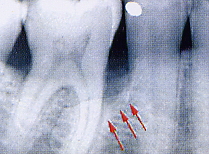

Aspetto radiografico della lesione prima della chirurgia |

Aspetto radiografico della lesione dopo chirurgia. Si noti la completa ricostruzione dell’ osso di sostegno. |